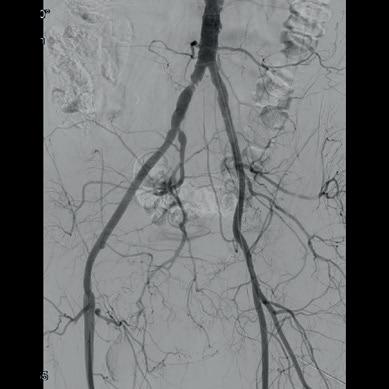

Multicentre experience shows “promising” midterm outcomes with IVL for calcified iliac occlusive disease

Shockwave intravascular lithotripsy (IVL) “expands endovascular strategies for iliac occlusive disease and can facilitate a ‘leave nothing behind’ approach,” Stefano Fazzini (Tor Vergata University, Rome, Italy) and colleagues write in an open-access Journal of Vascular Surgery (JVS) paper highlighting midterm outcomes from the IVLIAC registry—a multicentre, retrospective study of prospectively collected data.

“CALCIUM REMAINS A CHALLENGE IN the endovascular treatment of iliac artery disease, affecting both procedural and long-term outcomes,” Fazzini tells Vascular News. He goes on to comment that the standard approach of primary stenting, “although effective, is susceptible to stent recoil and under expansion in heavily calcified vessels” and notes that extensive calcification increases the risk of ruptures, especially when high-pressure balloons or balloon-expandable stents are used.

Fazzini also stresses that “no single stent is ideal for all calcified iliac lesions,” and that unnecessary stenting, especially at the bifurcation or when covering key branches, “can be avoided”.

In light of this, Fazzini et al set out to evaluate the midterm outcomes of patients with calcified iliac lesions treated with IVL, with or without adjunctive stenting, and to propose a new algorithm guiding these different treatment strategies.

The new algorithm, Fazzini explains, is based on lesion type (stenosis versus chronic total occlusion) and intraoperative functional assessments (extravascular ultrasound and pressure gradient) to determine whether stenting is necessary. “The impact

of sonic pressure waves improves vessel compliance and luminal gain, but such modifications may not always be evident on digital subtraction angiography alone,” he says, adding that intraoperative functional assessments play a “crucial” role in determining whether IVL alone is enough.

The investigators included all consecutive patients at four centres (Rome, Milan, Negrar and Trento) who underwent treatment with the Shockwave Medical peripheral IVL system for calcified iliac arteries from February 2021 to May 2024. Indication for IVL was Rutherford category of three or above in iliac lesions with moderate-to-severe calcification and was based on the new algorithm. The primary endpoint was primary patency, with assisted primary patency, secondary patency, and freedom from iliac complications also analysed.

Fazzini and colleagues share in JVS that a total of 100 iliac arteries were treated in 86 patients. They note that chronic limb-threatening ischaemia (CLTI) was present in 55% of patients, mean target lesion length was 40.95±29.25mm with a mean stenosis of 84±10%, and 12 of the lesions were chronic total occlusions. The authors report that technical

success was 99% and that target lesions were treated with IVL alone in 77% of cases, whereas IVL plus adjunctive stenting was employed in the remaining 23% of the cases. They add that provisional stenting was performed in 11% of cases, while planned stenting was performed in 12%, and that mean residual stenosis was 14.95±14% at final angiogram. Primary patency and assisted primary patency at 24 months were 95% and 98%, respectively, while secondary patency was 100%. Primary patency showed no statistically significant difference between the IVL only and IVL plus adjunctive stenting groups.

“Shockwave IVL offers a safe and effective treatment option for calcific iliac occlusive disease,” the authors write in their conclusion. “This multicentre experience shows promising midterm results in terms of primary patency despite the very low stenting rate, preserving future treatment options.” They go on to stress that further studies are needed to confirm these findings.

Discussing the findings with Vascular News, Fazzini summarises that, in cases of severely calcified disease, “Shockwave IVL as a first-line strategy in iliac interventions allows for either the avoidance of unnecessary stenting or optimisation of stent expansion, both of which contribute to favourable midterm outcomes”.